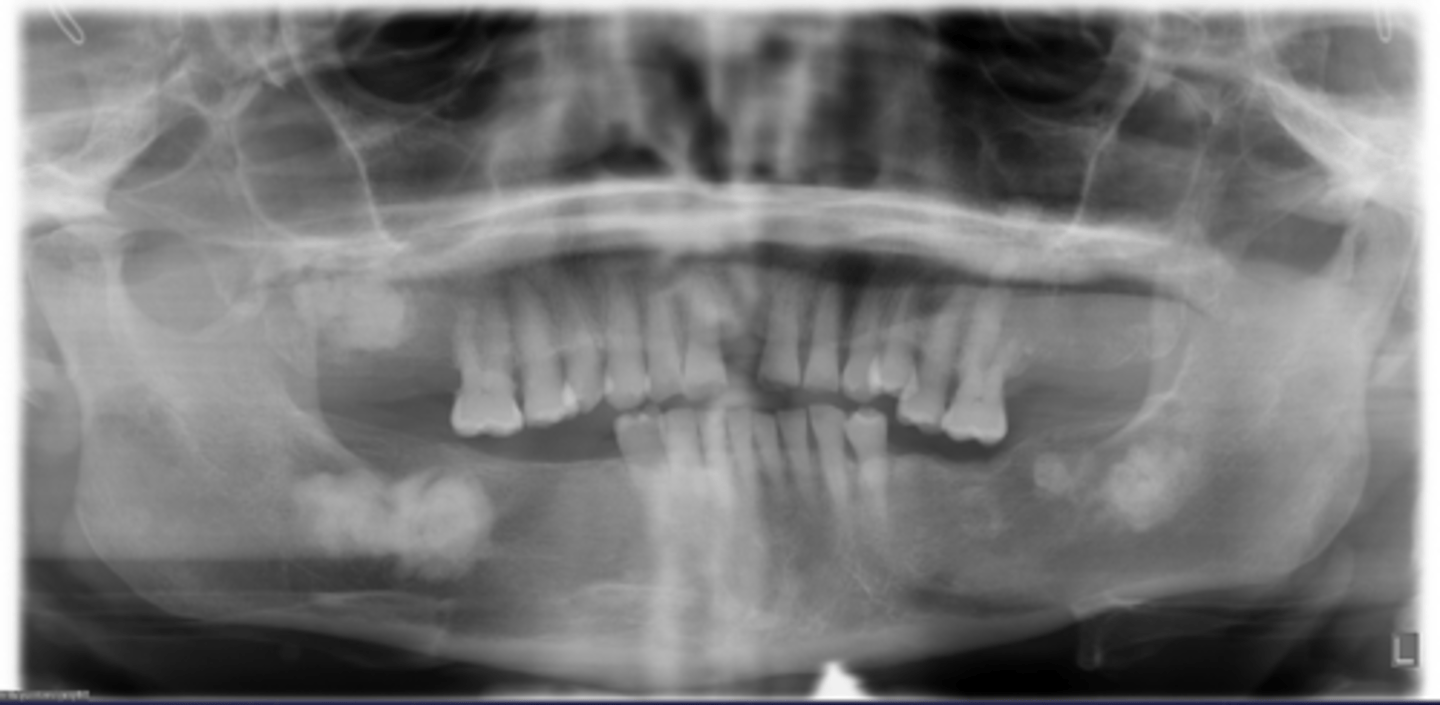

How would you describe the following lesion?

Multiple mixed density periapical target-like entities

The teeth are vital. What category would you put this lesion into?

dysplasia (PCOD)

what could be a differential diagnosis for this lesion?

A. radicular cyst

B. periapical granuloma

C. PCOD (stages 2/3)

D. apical rarefying osteitis